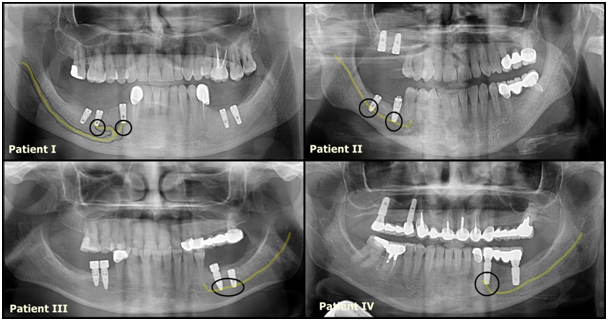

The subjects of this study consisted of 4 (2 male, 2 female) patients with an age range of 50–61 years with a mean of 55.25 years. In these 4 patients, the complaint was post‒surgical numbness in the lip and mucosal areas after implant operation between 8 and 12 months. The implants were seen to be related to the alveolar inferior nerve in post‒operative x‒rays (Figure 1). Patients participating in the present study do not have any previous neurological disorders.

Figure 1 Implants and Nervous Position in Orthophantogram.

In addition, the panoramic radiographs of Patient I showed the implant material and mandibular canal are close and there has seen bifid mental nerve (Figure 2). Ridge‒Split osteotomy was performed on alveolar bone and the implant was placed in the lower right 5th and 7th tooth regions to Patient I. In the Patient II two implants placed in mandibular molar region and numbness on the lip corner occurred in Patient I and II. At patient III and IV, there was numbness in the right lower jaw area and the mucosal area of canine teeth.

There is no consensus that CBCT scanning or CT effectively reduces IAN damage. Orthopantomography can be useful in implant planning.36 However, strict guidelines do exist enforcing the use of cross‒sectional imaging if required to better assess the IAN when routine radiography is inadequate.22 OPGs and other two‒dimensional radiographs have disadvantages to show the buccolingual aspect and cross‒sectional slices and patient positioning, magnification distortion and superposition of the anatomical structures.37,38 In our study, CT was taken after the procedure and there was a correlation between implant and nerve (Figure 1). In order to facilitate drilling efficiency, many implant drills are slightly longer than their corresponding implants and it is possible that the rate of nerve damage39,40 In this regard, it is important for the surgeon to be aware of the variations that exist in implant drill length. However, in patient III, the size of the implant used and the drill is same. It is estimated that the compression of the implant results in numbness at the lower right lip. Instead of surgical removal of the implant, not to lose implants, the patient was treated with LLT therapy. It is advisable to take an operation preliminary CT or prepare implant guide plates.